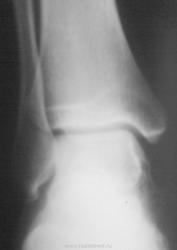

Сустав этот выглядит необычно. Нет ли подвывиха? Нужна прямая проекция.

Мне не понравилась: 1) Разница ширины рентгеновских суставных щелей (стрелки).

2) С чем это пяточная кость сочленяется? Где кубовидная? Не слилась ли она с ладьёй?

тогда нужно доснять голеностоп в боковой проекции на чуть большую пленку и переднююю часть стопы, а также другую ногу. или автор все это уже имеет?

Я думаю, что это из-за немного вольной проекции.